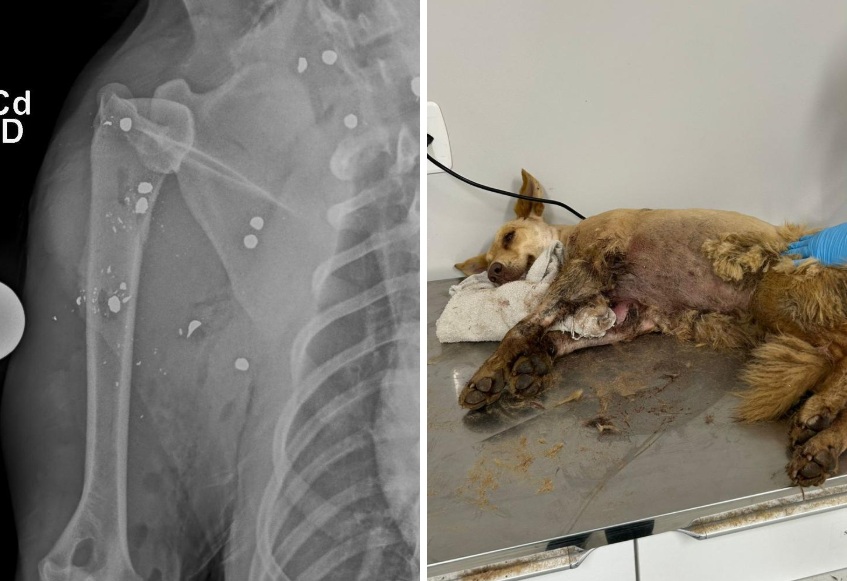

Cadela é resgatada com mais de 20 projéteis de chumbinho no corpo em Gaspar

A Prefeitura de Gaspar, por meio da Diretoria do Bem-Estar Animal, atendeu na segunda-feira (27) uma denúncia de maus-tratos contra uma cadela no bairro Belchior Central. O caso chocou a comunidade local. Após ser resgatada, o animal foi encaminhado a uma clínica veterinária, onde exames revelaram mais de 20 projéteis de chumbinho espalhados pelo corpo.

A cachorra passou por uma cirurgia de emergência e segue internada, recebendo cuidados intensivos. Segundo a Diretoria, o pedido de ajuda partiu de moradores da comunidade, que já conheciam e cuidavam do animal. Ao encontrá-la ferida e assustada, eles acionaram a equipe municipal para o resgate imediato.

Fotos: Divulgação / PMG